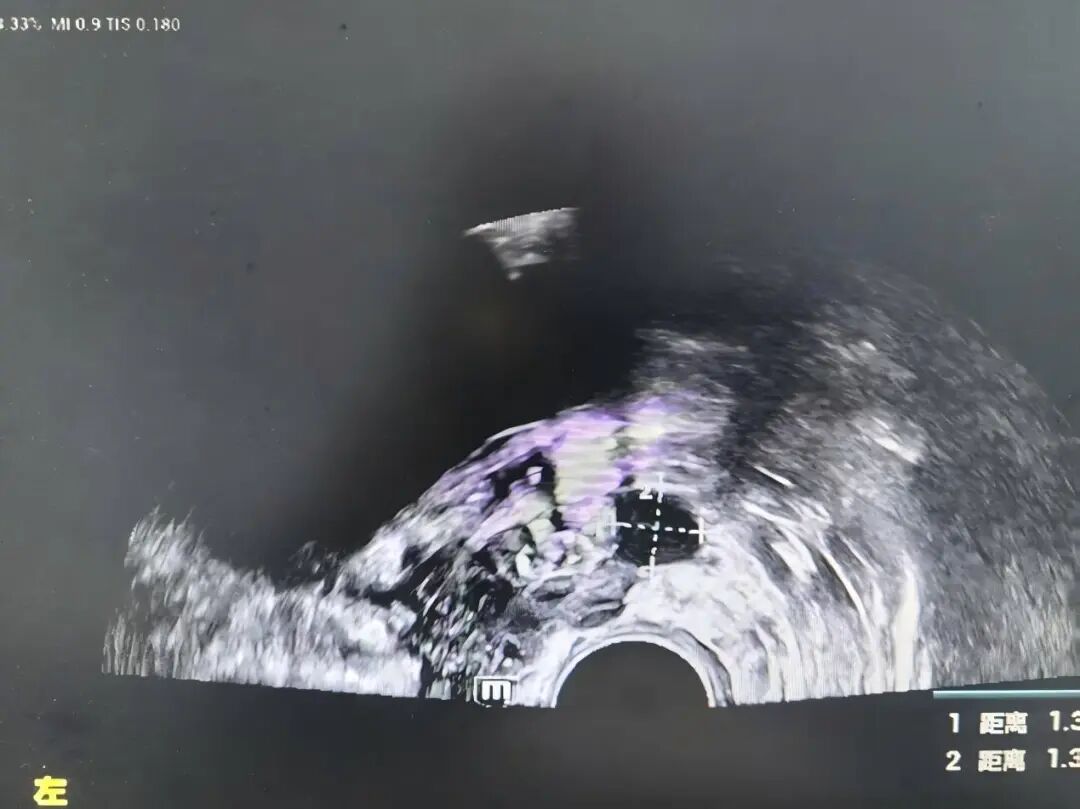

前列腺恶性肿瘤 是男性常见的泌尿系统肿瘤之一 当病情步入中晚期 治疗的关键在于结合系统治疗 一项能够直击病灶 持续作用的微创技术 为综合治疗拓展了新的可能 近日,贵州航天医院泌尿外科团队成功开展一例超声引导下经会阴前列腺碘125粒子植入术,为患者制定了个体化治疗方案。 案例分享 近期,一位年近八旬的男性患者因左侧髋部不适伴下肢放射痛前来就诊,初步检查提示可能存在前列腺肿瘤伴骨转移,为进一步明确诊断,患者随即转入泌尿外科诊治。泌尿外科为患者完善了相关检查,随后在超声引导下实施了经会阴前列腺穿刺活检,结合磁共振(MRI)影像与病理结果,最终明确诊断为前列腺腺癌(T4N0M1)。 考虑到患者年纪较大、身体状况比较弱,加上肿瘤已是晚期,已不适合创伤较大的前列腺癌根治性切除手术。为提供更佳的治疗方案,泌尿外科组织呼吸与危重症医学科肿瘤病区的专家进行了多学科讨论评估,征得家属同意后,定了一个分两步走的治疗方案:先实施前列腺肿瘤碘125粒子植入微创手术(把带辐射的小粒子放到患处杀灭肿瘤细胞),手术后,再配合药物(内分泌治疗)来控制病情。手术过程顺利,患者恢复良好,目前已出院并定期随访中。 术后植入粒子影像 我院多学科诊疗(MDT)已成为应对复杂疾病的常规模式,通过整合多学科的资源与优势,汇聚外科、内科、肿瘤、微创介入、影像、检验等多学科专家进行会诊,突出个体化治疗和综合全面治疗,提高诊疗效率和精准性,避免患者在多个科室间反复挂号奔波,缩短诊疗等待时间,让广大肿瘤、疑难重症患者享受到更加优质、专业、“一站式”的诊疗服务。 什么是放射性粒子植入技术 放射治疗是肿瘤治疗的常见手段之一,主要包括外照射与近距离放射治疗,碘125粒子植入属于持续低剂量率近距离放疗的一种,将微型放射性粒子永久植入前列腺组织内,通过持续释放射线作用于肿瘤区域,治疗前需通过影像学检查精确评估前列腺形态、体积,并制定个体化的剂量分布计划,术中在超声实时引导下植入粒子,以便根据实际情况调整进针路径与剂量分布,尽量使射线覆盖前列腺及其周边一定范围。该技术通常适用于部分局部进展性或转移性前列腺肿瘤患者,可作为综合治疗策略中的一环。 放射性粒子植入技术优势 1.能够把粒子准确植入肿瘤中,定位精准,靶向性强,高度适形。 2.肿瘤接受的放射剂量明显增加,而不增加正常组织的剂量。 3.持续低剂量率放射,能对不同分裂周期的肿瘤细胞进行不间断照射,提高了放射敏感性,累计射线剂量可达外放疗的2~3倍,有较高的放射生物效应。 4.粒子植入的部位肿瘤组织可被杀灭,距粒子1cm以外的正常组织几乎不受损伤,能有效降低正常组织受照剂量,正常组织损伤小,几乎不造成白细胞下降、骨髓抑制、胃肠道反应、脱发等副作用,病人无痛苦。 5.粒子外壳为钛合金,与人体有很好的组织相容性,不会产生排异及放射泄漏。 6.与其他的肿瘤治疗方法相比,创伤小、生活质量高、住院时间短。 7.能与手术、化疗及外放疗配合互补提高疗效。 注:本文仅为医疗技术介绍,具体治疗方案请务必咨询临床医生,并结合患者个体情况制定。部分图片来源于网络,如有侵权,请联系删除。 贵州航天医院 泌尿外科专家简介 石 英 泌尿外科党支部书记、主任,主任医师 中国医师协会泌尿外科分会感染协作组委员,奥林巴斯泌尿系软镜西南区专家组成员,西南地区第一批输尿管软镜专家组成员,贵州省医学会泌尿外科分会委员,贵州省性学会理事,贵州省性学会常务委员,贵州省泌尿外科专业医疗质量控制中心专家委员会委员。 从事泌尿外科专业近30年,熟练掌握泌尿系各类疾病的诊治,具有丰富的临床经验,擅长泌尿系结石、腹膜后肿瘤及泌尿系肿瘤的手术治疗,对泌尿系感染、泌尿系结核、尿源性脓毒血症的救治有独到的见解及抢救经验,在贵州省率先引入输尿管软镜技术,同时在男科领域,对男性阳痿、早泄及前列腺疾病有很深的研究。 李国成 泌尿外科副主任,副主任医师 中国人体健康科技促进会男科学专业委员会委员,贵州省性学会泌尿外科分会委员,贵州省医学会男科学分会委员,遵义市医学会男科学分会副主任委员兼秘书长,遵义市医学会泌尿外科分会常务委员,贵州航天医院男科带头人。 从事泌尿外科及男科工作10余年,曾多次前往上海交通大学附属第一人民医院、中国中医科学院西苑医院进修学习男科;擅长性功能障碍的诊治、男性整形手术、前列腺增生激光手术、显微手术等。 李 凯 中共党员,泌尿外科副主任医师 贵州航天医院肿瘤腔镜组带头人,擅长肾癌根治术、输尿管癌根治术、膀胱及前列腺癌根治术、腹腔镜输尿管狭窄切除吻合术、输尿管切开取石术等手术,在遵义市率先开展泌尿系结核后膀胱挛缩全腹腔镜下膀胱扩大术。 贵州省医学会泌尿外科分会青年委员,遵义市医学会男科分会常务委员,遵义市医学会泌尿外科分会常务委员。 贵州航天医院泌尿外科简介 • ✦ 基本情况 ✦ • 贵州航天医院泌尿外科创建于20世纪60年代,经过几代人的努力,微创与内镜手术占比达90%以上,科室亚专业框架完善。是贵州省临床重点专科建设单位、北京清华长庚医院李建新教授团队诊疗及会诊中心、北京医学会尿路修复与重建诊疗及会诊中心、上海公济泌尿外科集团遵义中心、上海援黔专家李铮教授男科工作室、贵州省泌尿外科质量控制专家委员单位。 • ✦ 专科特色技术 ✦ • (一)泌尿系结石内镜碎石技术 泌尿系结石微创治疗领域方面是贵州省首家引进科医人钬激光碎石技术科室,在遵义地区率先掌握输尿管硬镜、软性镜,经皮肾镜钬激光碎石技术。目前是北京清华长庚医院泌尿外科“手把手”经皮肾镜碎石技术培训基地、贵州省输尿管软镜培训基地。 1.负压吸引可弯曲软镜鞘电子软镜碎石术 2.标准与超微通道相结合的经皮肾镜碎石取石术 (二)微创腹腔镜技术 泌尿外科腹腔镜技术师承于浙江省人民医院、北大、北京解放军总医院。目前采用经腹、经后腹双入路法的腹腔镜技术完成肾部分切除、肾切除、肾输尿管全长切除、肾盂输尿管成形、输尿管狭窄吻合、膀胱翻瓣等手术。在遵义地区率先掌握腹腔镜下膀胱癌根治术、腹腔镜下前列腺癌根治术。 (三)男科、盆底技术临床应用 遵义地区男科分会主委单位,是贵州省首家引进尿动力学检查并取得了全国资质认证科室,也是贵州省首家进行RigiScan检查的单位。在遵义地区率先掌握显微取精子技术以及显微镜下治疗精索静脉曲张、显微镜下输精管吻合、输精管附睾吻合技术。率先采用前列腺激光剜除术治疗前列腺增生症。在陆军军医大学西南医院泌尿外科主任沈文浩教授指导下,完成遵义市首例神经源性膀胱骶神经调节刺激器置入术。 • ✦ 诊疗范围 ✦ • 诊疗范围(除外肾移植、癌栓):泌尿系结石、泌尿系肿瘤、肾上腺疾病、肾积水、前列腺增生、男性生殖器功能障碍(精索静脉曲张、生殖道感染、输精管梗阻等)、盆底功能障碍性疾病(膀胱脱垂、排尿功能异常、尿失禁)、泌尿生殖系畸形。 泌尿外科拥有独立门诊治疗室、日间手术室、尿动力学检查室、精液分析检查室、男性勃起功能检查及治疗室、ESWL治疗室、结石分析检查室。